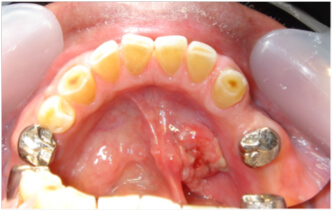

口底がん